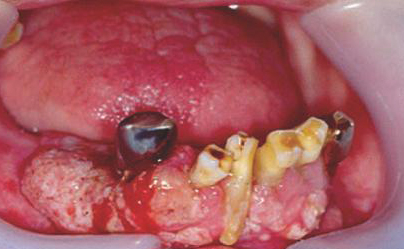

흡연은 폐암의 주요 원인으로, 전체 폐암 환자의 약 85~90%가 흡연과 직접적으로 관련이 있습니다. 또한 폐암뿐 아니라 구강암, 후두암, 식도암, 췌장암, 방광암 등 다양한 암 발생 위험을 높입니다. 담배 속의 타르, 니코틴, 벤젠과 같은 발암물질은 체내 세포의 DNA를 손상시켜 암세포의 성장을 촉진합니다.